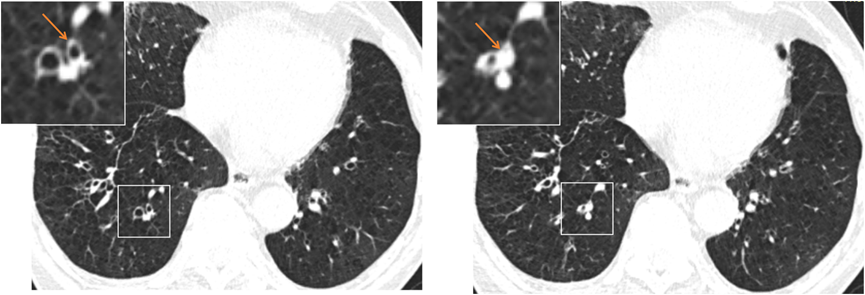

这项研究为一项单中心前瞻性观察性队列研究,纳入了194例在2017年8月至2022年7月期间就诊于广州医科大学附属第一医院并符合GOLD诊断标准的稳定期COPD患者。患者随访1–2年,通过电话和门诊评估并记录急性加重事件(门诊需抗生素/口服激素治疗或经急诊、住院治疗)。按 Netter 支气管解剖分 18 个肺段,每个肺段有黏液栓(图1)计1分,无则计 0 分,总分为 0~18 分。根据黏液栓累及肺段数分为3组:0、1–3、≥4分。

图1 在自上而下的轴向连续切片中 RB10 节段黏液栓形成过程,左图箭头示部分阻塞气道,右图箭头示黏液栓完全阻塞。